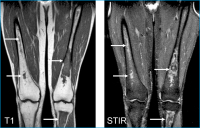

Hüftkopfnekrose

Abbildung 2: MRI T1, STIR und Röntgenübersicht Beckenregion: Avaskuläre Hüftkopfnekrose links mit sekundärer Defomierung und sklerotisch, degenerativen Veränderungen des Hüftgelenkskopfes (Pfeil).